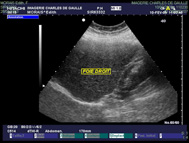

| L’examen est basé sur l’utilisation des ultrasons. |

| Une sonde placée au contact de la peau, émet des ultrasons qui arrivent au contact des organes et reçoit la réponse qui est transformée en image. |

| Tous les organes pleins peuvent être explorés en échographie : foie, vésicule, pancréas, reins, vésicule biliaire, vessie, utérus, ovaires, thyroïde, muscles, seins. |